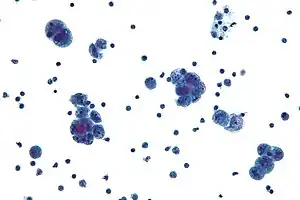

Micrograph of serous carcinoma, a type of ovarian cancer, diagnosed in peritoneal fluid

Diagnosis of ovarian cancer starts with a physical examination (including a pelvic examination), a blood test (for CA-125 and sometimes other markers), and transvaginal ultrasound.[20] Sometimes a rectovaginal examination is used to help plan a surgery.[23] The diagnosis must be confirmed with surgery to inspect the abdominal cavity, take biopsies (tissue samples for microscopic analysis), and look for cancer cells in the abdominal fluid. This helps to determine if an ovarian mass is benign or malignant.[20]